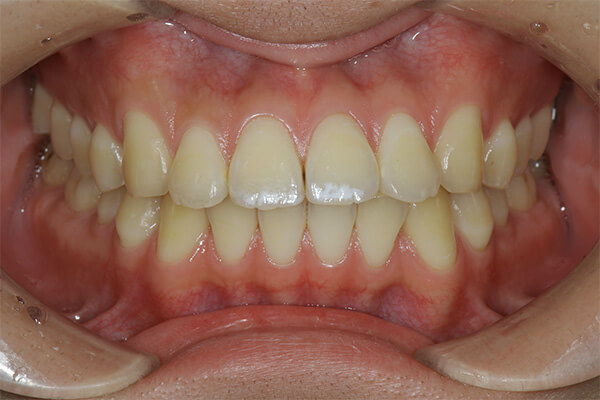

上の前歯の古い被せ物を治したいと言うことで来院されました。上下の前歯は少しガタガタになっており、奥歯には古い金属の詰め物が見られます。

上の前歯の被せ物が長い期間保つようにするためには、下の前歯のガタガタを整えておく必要があります。この症例くらいのガタガタであれば、インビザラインGoを使えば短期間で綺麗に治すことができます。歯並びが整ったことで治療のモチベーションが上がり、ホワイトニングと奥歯の銀歯を全てセラミックに置き換える治療を行い、金属がない(ノンメタル)状態になりました。